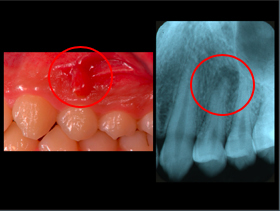

歯周病

デジタルXray写真(2次元)

CT 3D画像

3枚の写真、赤丸部分が歯周病により歯の周りの骨が吸収しているのが認められます。

CT画像(3次元)